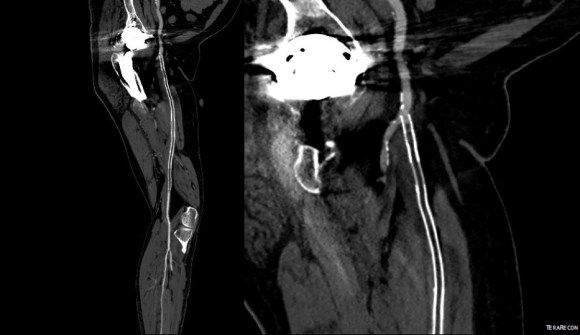

The patient came back in followup -it has been 4 years since his infection was repaired. He was complaining of short distance claudication. His wound healed well and remains closed. CTA shows along with his short segment SFA occlusion which we will treat, a widely patent R. EIA (below).

The remote endarterectomy of the external iliac artery remains patent. Compare this to the preop CTA which I found and wasn’t available when I posted this case originally:

The chronically occluded EIA can be readily seen. The artery shown in the current CTA is that recanalized artery.

CTA (pictured above and below) showed a 5.1cm infrarenal AAA with an hourglass shaped neck with moderate atherosclerosis in the neck, an occluded left common iliac artery with external iliac artery reconstitution via internal iliac artery collaterals, and a right external iliac artery occlusion with common femoral artery reconstitution. There was calcified right common femoral artery plaque.

The patient recovered well and was sent home several days postprocedure. He returned a month later with healed wounds and palpable peripheral pulses. He no longer had claudication and CTA showed the aneurysm sac to have no endoleak (figures below).